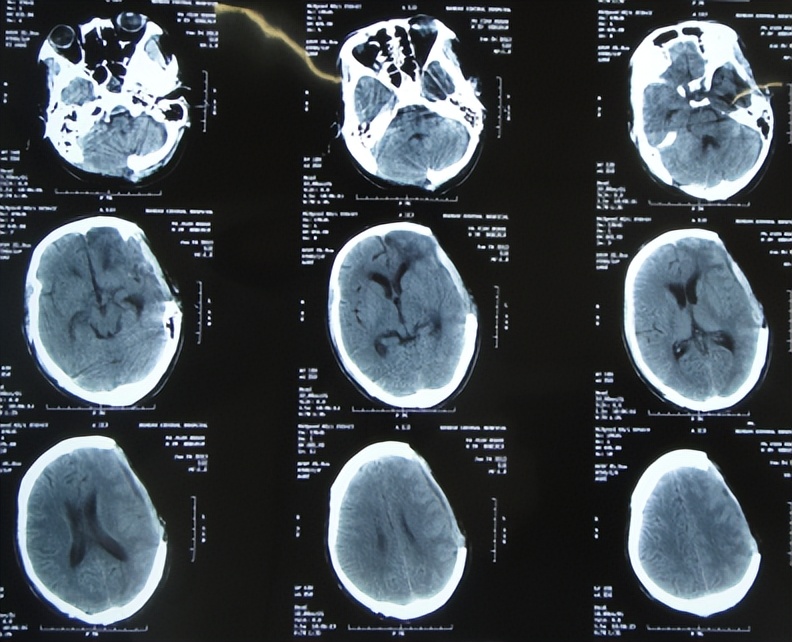

开颅术后11天,神志变醒,能简单言语;但开颅术后19天即2012年12月26日,发热最高体温38.5度,大小便*禁失**,查头颅CT是骨窗膨隆,脑室稍扩张( 图-5 );给予腰大池外引流术。

图-5: 2012年12月26日头颅CT

开颅术后28天即2013年1月4日(腰大池引流术后9天),认知能力好转,可自动进食,大小便可自控,但仍间断发热,查头颅CT示脑膨出变基本正常( 图-6 ),给予拔除腰大池引流管。

图-6: 2013年1月4日头颅CT

转院后继续行腰大池引流术,给予万古霉素、头孢哌酮钠及头孢曲松等抗炎治疗,开颅术后32天即2013年1月8日,查头颅CT认为脑室基本正常,但仍有水肿( 图-7 )。

图-7: 2013年1月8日头颅CT

但拔除3天后即2013年1月27日(开颅术后51天),患者意识再次变差昏迷不醒,查头颅CT示,脑积水加重,骨窗组织膨出( 图-8 );右侧肢体肌张力增高、力量减弱,大小便再次*禁失**,继续给予腰大池引流。

图-8: 2013年1月27日头颅CT

腰大池引流术后21天即2013年2月17日(开颅术后72天),查头颅CT示脑室缩小,骨窗变塌陷( 图-9 ),再次拔除腰大池引流管。

图-9: 2013年2月17日头颅CT

但腰大池拔除术后10天即2013年2月27日(开颅术后82天),患者再次意识不清,大小便*禁失**,查头颅CT示脑积水,脑膨出( 图-10 )。

图-10: 2013年2月27日头颅CT